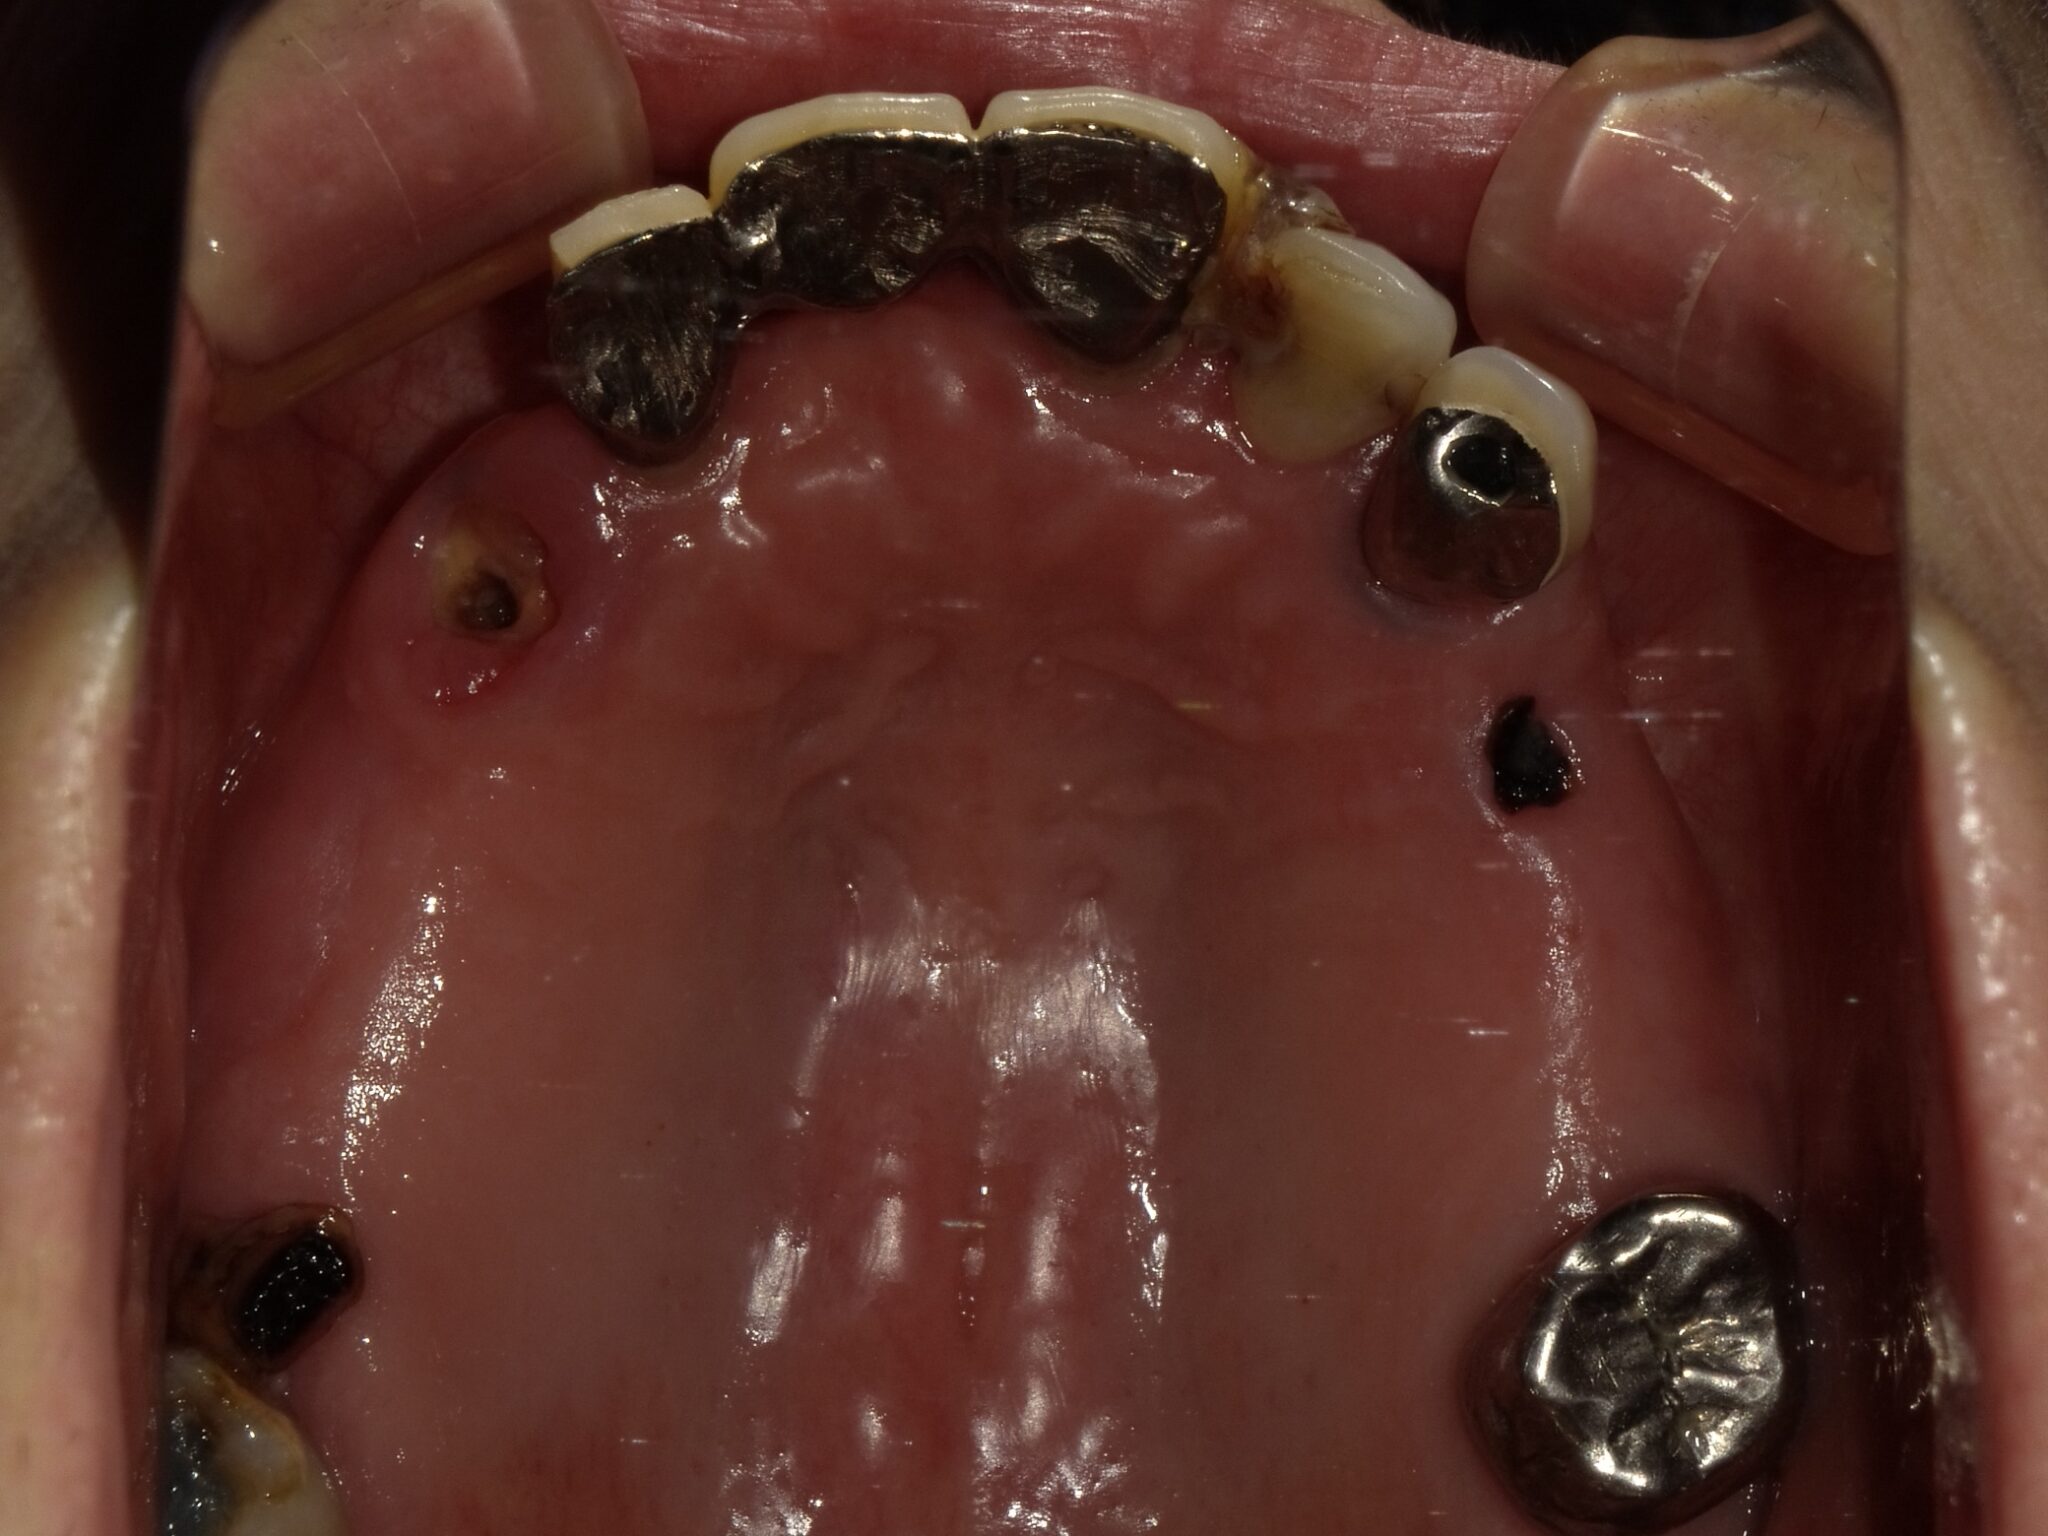

全顎治療症例

| 主訴 | 全体的に見た目を綺麗にしたい。奥歯でしっかり噛みたい。 |

| 診断名・ 主な症状 |

臼歯部欠損 |

| 治療内容 | インプラント埋入(右上4・6,左上4・6,右下6,左下6) ジルコニアBr(右上3―左上3) ジルコニア(右下5,左下5) |